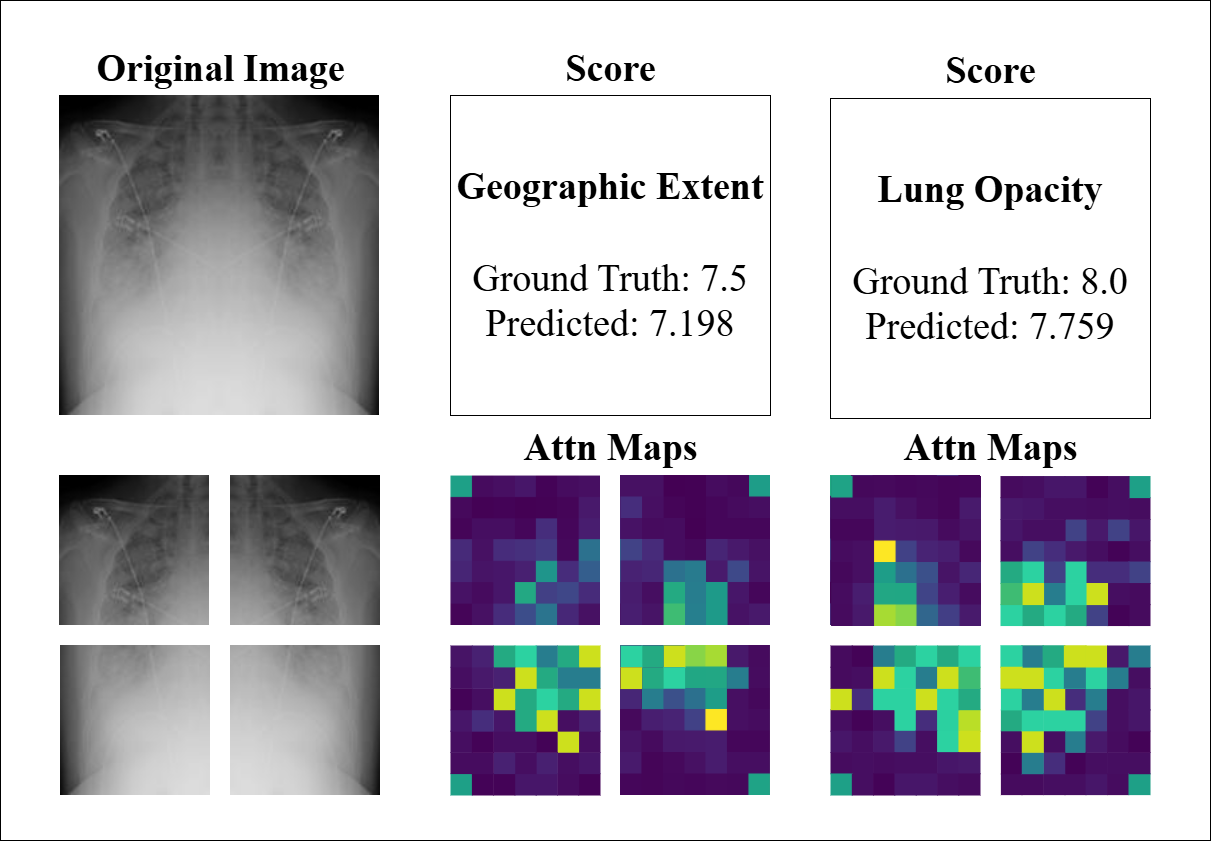

4.4 Model Interpretability

To further evaluate the interpretability and consistency of our model, we conducted a visual inspection of attention maps and prediction outcomes across representative CXR and CT cases. Figure 7 displays three CXR examples alongside their corresponding quadrant-wise attention maps that represent the output of the four PVT encoders, as well as the GT and predicted scores for both GE and LO. The attention maps demonstrate the model’s ability to localize clinically relevant radiographic features, with predictions largely consistent with GT scores (e.g., LO: GT 3.0 vs. predicted 2.714). Notably, the attention weights align with the predicted severity, as the model’s scores reflect the proportion of high-weight regions within the maps. However, the last example (GT 2.5 vs. predicted 5.86) exhibits a significant deviation. While the attention maps highlight diffuse areas of activation, the overestimation may arise from image-quality limitations, such as low contrast or anatomical noise, which could lead the model to misinterpret benign variations as pathological findings. This underscores the influence of technical artifacts on model performance and highlights the need for robust preprocessing to enhance reliability.